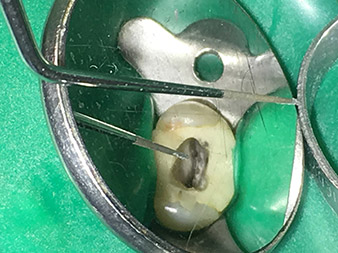

Наред с ефективната диагностика и методите на лечение, използването на най-новите технически средства и инструменти също има важен принос за успешната грижа за пациента. Д-р Шарад Нураие Аштиани и екипът му в денталната практика в Бремен, Германия третират до десет ендодонтски случая на седмица. Желанието на пациента за възможно най-атравматично лечение в комбинация с добри прогнози за успех представлява ежедневно предизвикателство за лекарите по дентална медицина.

Като запален потребител на разширената W&H гама от накрайници за ултразвукова ендодонтия, Д-р Нураие Аштиани не само е в състояние да извърши по-ефективно кореново лечение, но и да го направи по начин, който натоварва по-малко пациента. Денталните експерти се справят с лекота дори с най-трудните ситуации. В скорошно интервю, специалистът в ендодонтията ни разказа за особеностите, които характеризират W&H накрайниците и посочи възможните рискове, които могат да възникнат при кореново лечение.

Снимки: Д-р Шарад Нураие Аштиани, Бремен